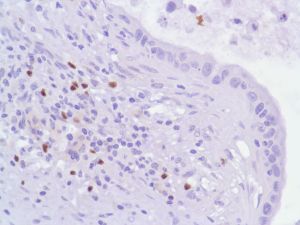

FoxP3 (SP97)

FOXP3 (a 431 amino acid protein) is a member of the forkhead/winged-helix family of transcriptional regulators and is highly conserved across mammals. FOXP3 is essential for normal immune homeostasis. FOXP3 is stably and constitutively expressed at a high level in CD25 + CD4 positive regulatory T cells, at a low level in CD4 positive/CD25 negative cells, and is absent in CD4 negative/CD8 positive T cells. FOXP3 may be a master regulatory gene and a more specific marker of regulatory T cells than other T cells.